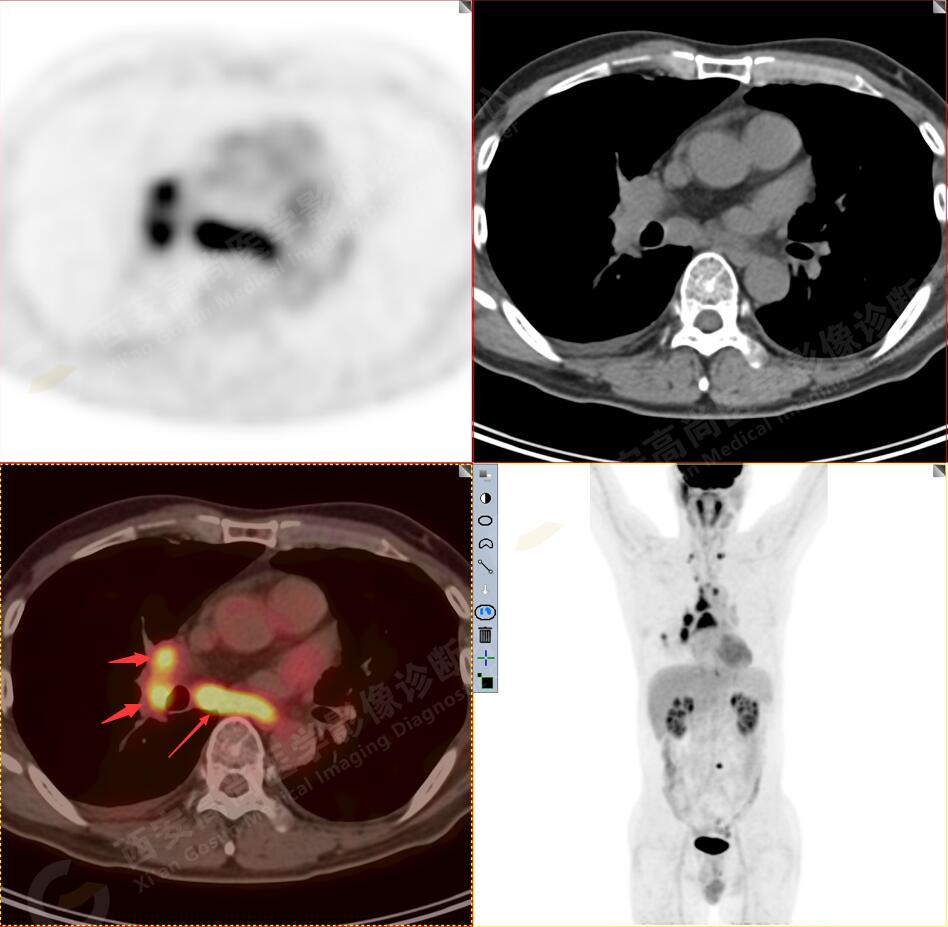

1.以下為肺內(nèi)原發(fā)灶

2.以下為全身多發(fā)轉(zhuǎn)移灶

1.右肺下葉后基底段軟組織結(jié)節(jié)(約1.5cm×1.2cm),與相鄰后胸膜分界不清,呈FDG代謝異常增高,結(jié)合病理,符合肺腺癌伴鄰近胸膜侵犯。

2.雙肺多發(fā)高密度小結(jié)節(jié)灶(最大徑約0.7cm),部分較大結(jié)節(jié)呈FDG代謝略增高,均考慮為轉(zhuǎn)移性病變。

3.右側(cè)肺門、縱隔(1L、1R、3A、4、6、7組)及雙側(cè)鎖骨上多發(fā)腫大淋巴結(jié),呈不同程度FDG代謝異常增高,考慮為淋巴結(jié)轉(zhuǎn)移。

4.右后胸膜輕度增厚,形成多個(gè)條狀軟組織病變,呈FDG代謝輕度異常增高,考慮為轉(zhuǎn)移性病變;右側(cè)胸腔微量積液。